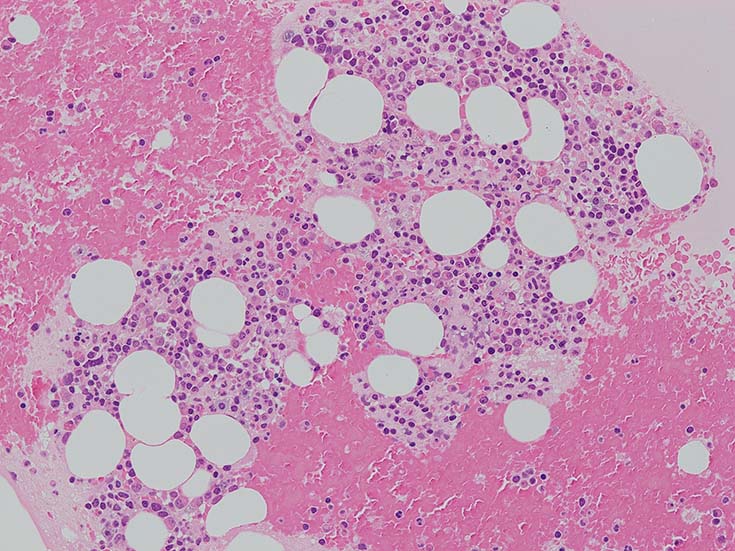

lymphoplasmacytic lymphoma(LPL)

Lymphoplasmacytic lymphoma cases

Case

56歳 女性

検診異常の再検査で受診, 慢性炎症, 小球性貧血, 血清IgM高値あり. 造血器疾患を疑われ血液内科で精査となった.

IgG 1365mg/dl, IgA 225mg/dl, IgM 1800(35-220)mg/dl. 血清免疫電気泳動で IgM-λtype M proteinを検出. 尿中 Bence Jones タンパク-λ型(+).

この症例では骨髄組織での造血巣内にリンパ球や形質細胞の軽度増加があるようだが, 腫瘍細胞増殖が明瞭ではない. 結節形成はみられない. mast cellsの増加がNaphtol-ASD-CAE染色で確認される.